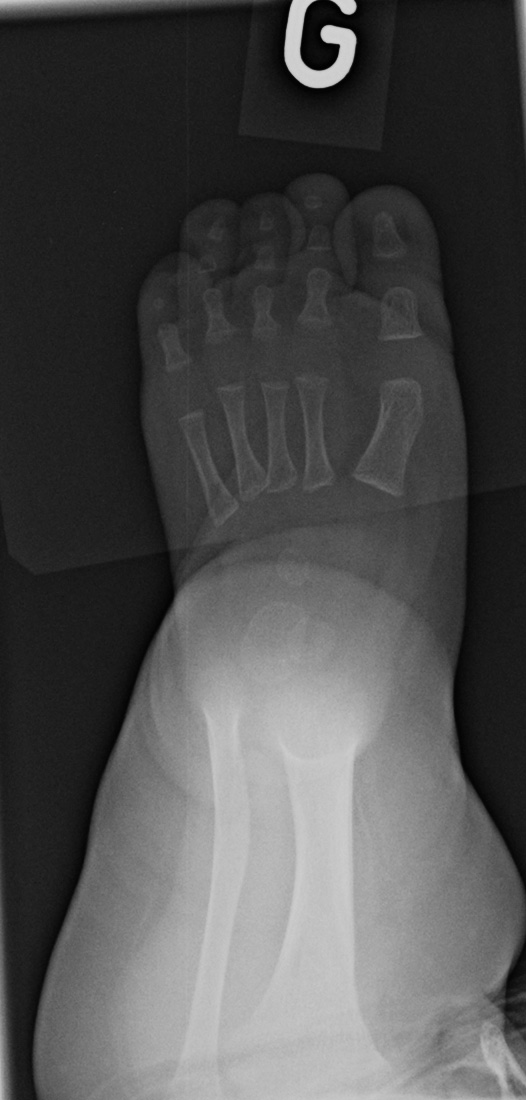

0-hour-old male:

Feet deformity.

On the right side, the anteroposterior talo-calcaneal angle (Kite's angle) is decreased to 7° (normal between 20 and 40°). On the lateral view of Turco, the talo-calcaneal angle is 30° (normal over 35°). In short, on the anteroposterior view, the talus and calcaneus are more parallel than expected (normaly they are diverging).

On the right anteroposterior view, the talus-1st metatarsal angle is measured at -7° (normal between 0 and 20°). The 1st metatarsal is medial to the talus because of the forefoot deviation in varus and adductus.

On the left side, the talus is not ossified enough to take measurements. Global alignment, however, suggests a left club foot of similar severity than the right.